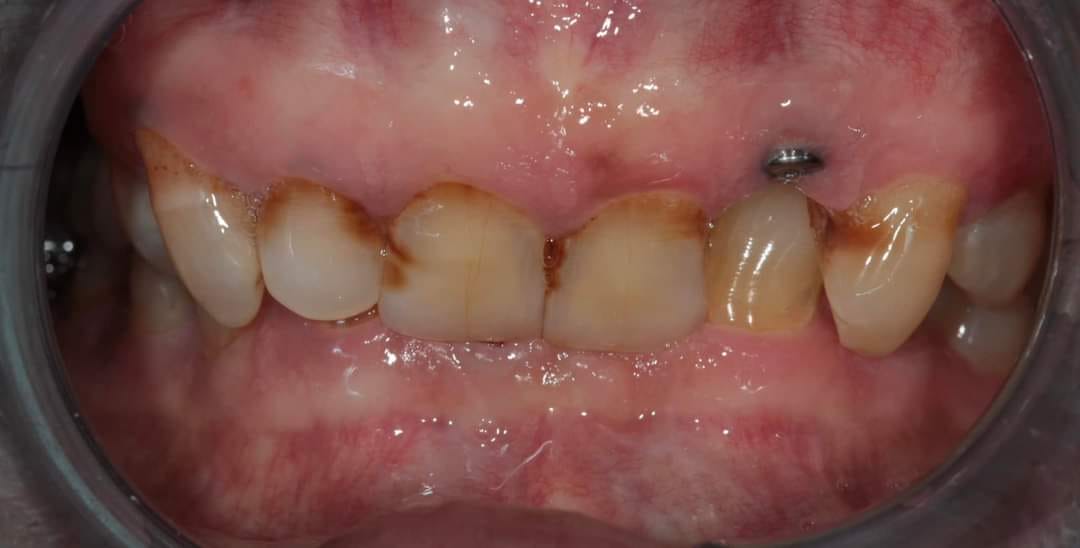

Before

Before And After Full MouthRehabilitation Treatment